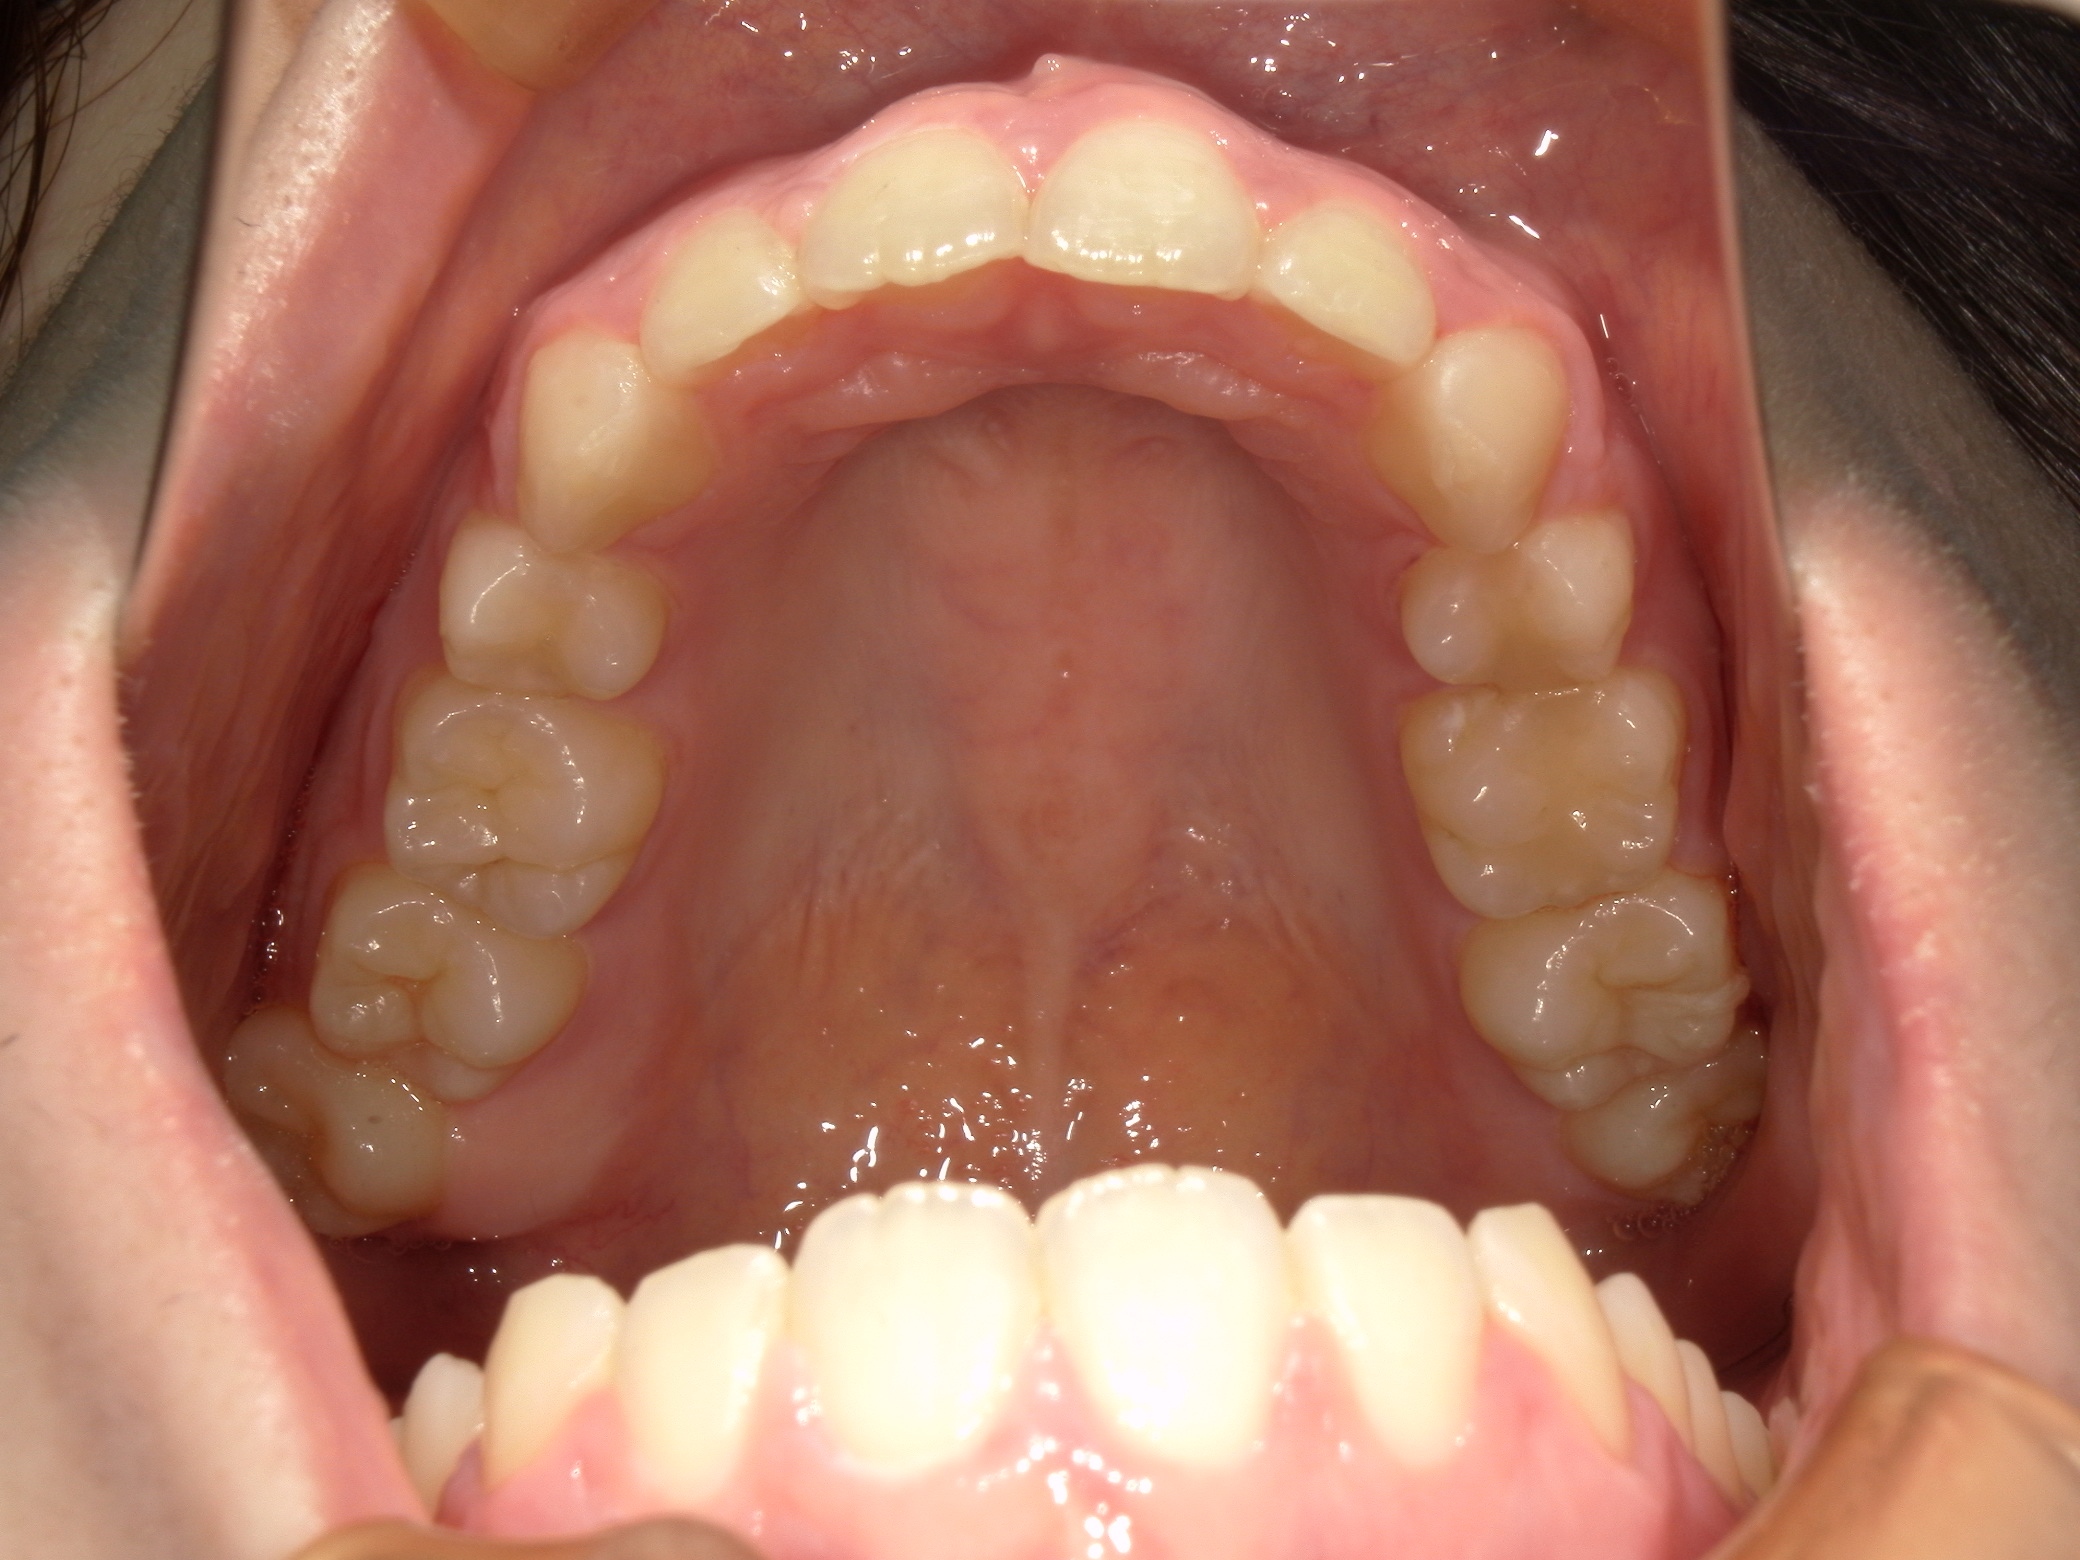

口内上

治療前

治療後

上の前歯に重なりがあることと口元が前突していることが問題となっていました。

上の前歯は唇側に傾斜しており、全体的に手前に倒れるような歯の配置となっていました

検査の結果、傾斜を治し、口元を内側に引き込むため、上下の歯を抜いてワイヤー装置で歯を並べることとしました

抜歯によって得られたスペースを十分に活かすことで、上の前歯の重なりと、口元の前突感、全体的な歯の傾斜を改善することが出来ました。